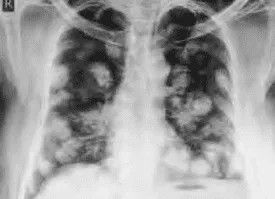

Hình ảnh “Di căn phổi bóng bay trên X-quang”.